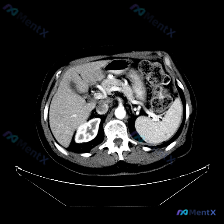

整理了一份上腹部CT(软组织窗)的病例,想和大家讨论一下。 先看病例信息: - 扫描层面:上腹部,肝脏上部及胃底层面 - 可见结构:肝右叶及左叶部分实质、胃底及胃体上部、腹腔、胸腔/膈肌、胸椎及其附件 - 关键发现:腹腔内可见明显的游离气体(肝脏前方及胃周围有深黑色区域),两侧膈下区域可见新月形低密...

最近看到一个有意思的影像病例,预设是要讨论「脾脏病变」,但看完影像报告和分析后,发现核心其实是「澄清矛盾」,整理一下思路和大家分享。 --- 先看完整的影像观察结果 这是一份腹部CT横断面的分析: - 实质脏器:肝、胰、脾、肾都大致正常——肝脏密度均匀,胰周脂肪间隙清晰,脾脏形态/大小正常、密度均匀...

今天看到一个有意思的影像读片案例:提问直接预设了“脾脏病变”,但仔细看完提供的资料,发现情况好像不太一样。整理了一下思路,和大家分享。 先看影像资料(客观描述) 这是一张上腹部CT横断面软组织窗影像,报告里的客观表现: - 肝脏:形态尚可,密度基本均匀,未见明确异常高低密度占位,边缘清晰,血管走行正...

今天看到一份很有意思的影像资料,提问直接指向“脾脏特异性异常”,但仔细读完图像和分析,发现里面藏着一个很典型的临床思维陷阱,整理一下思路和大家分享。 先看这张CT的客观发现 这是一张腹部CT横断面软组织窗图像: 1. 脾脏:形态可见,密度均匀,没有看到明确的增大,也没有局灶性的高低密度病变; 2....

整理了一份有点「反转」的影像读片资料,感觉挺考验临床思维的,分享出来一起理理思路。 --- 一、影像基本信息 这是一张腹部CT横断面软组织窗图像,预设的观察焦点是「脾脏病变」。 二、结构化读片所见(客观描述) 按照读片常规扫了一遍全腹: 1. 肝脏、胆囊、胰腺:形态、大小、密度都正常,轮廓光滑,胰周...

今天看到一个很有意思的影像分析场景,整理一下思路和大家分享。 --- 病例背景 用户提供了一张腹部CT横断面(软组织窗),并直接询问:“图片中可见的特殊异常是什么?脾脏病变”。 影像核心表现 我先按标准流程梳理了这张CT的关键信息: 1. 脾脏:大小、形态正常,脾实质密度均匀,明确未见占位、梗死或异...